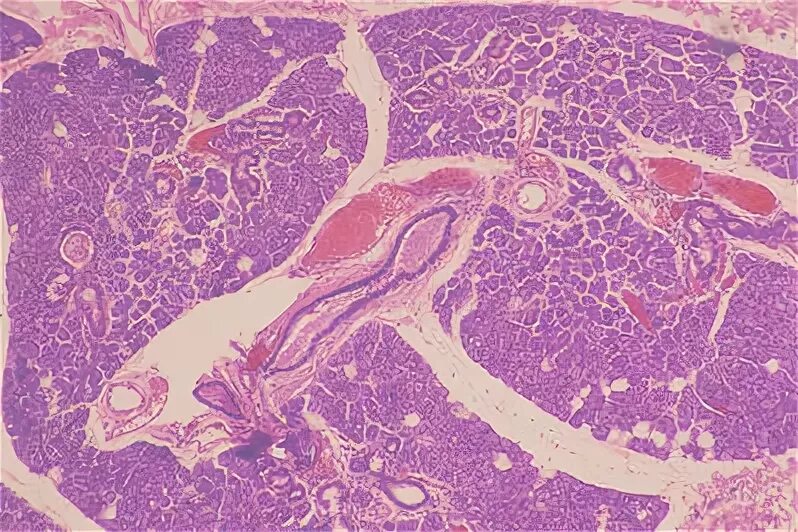

Гистология смешанный